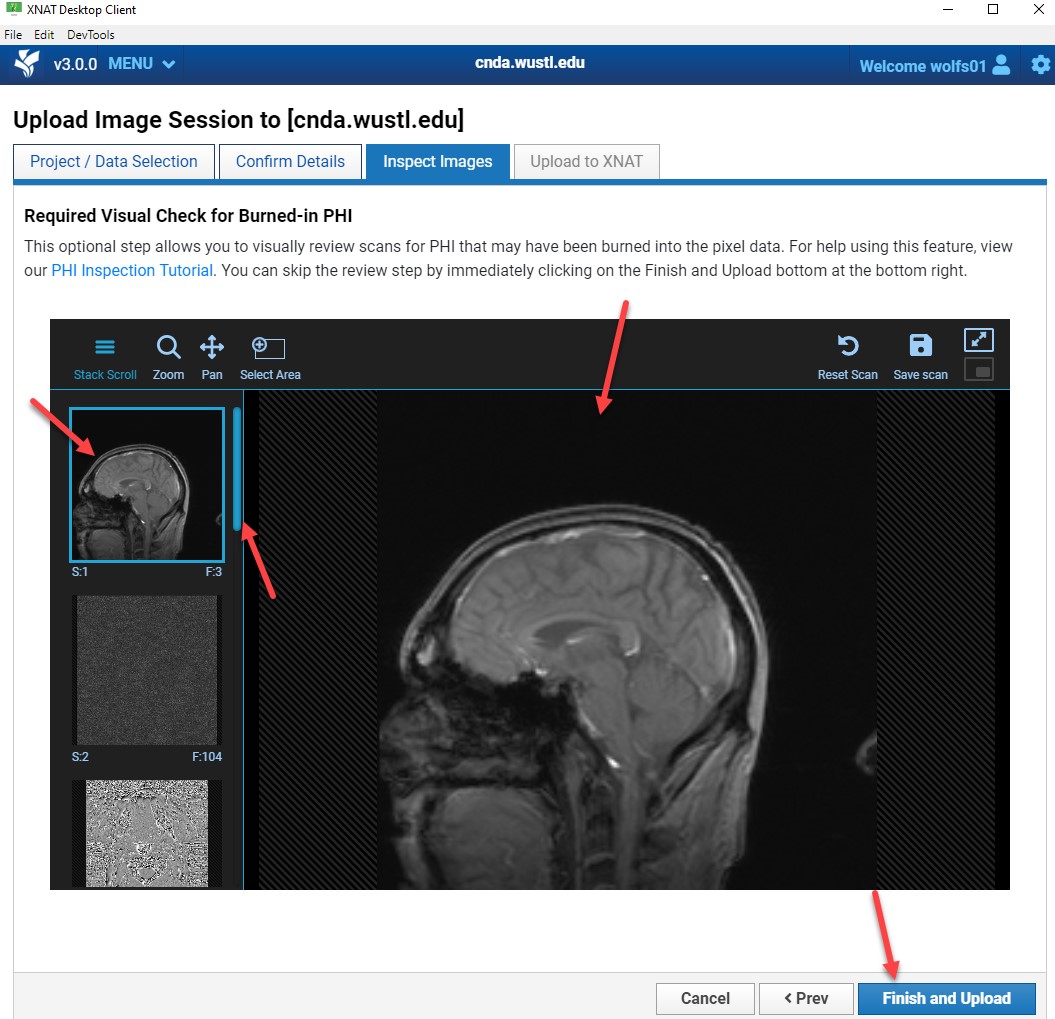

PHI Visual Inspection

All images must be reviewed for burned-in PHI.

PHI includes:

- Patient names

- Initials

- Medical record numbers

- Any identifying text

Review Steps

- Select a series from the left panel.

- Drag it into the viewer.

- Scroll through all images.

- Repeat for every series.

- Click Finish and Upload when complete.